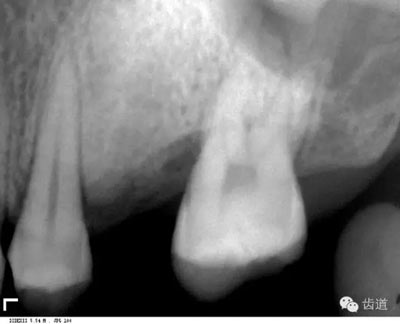

髓腔可分為冠部的髓室和根部的根管。牙髓內(nèi)含牙髓軟組織,X線片上顯示為密度低的影像。年輕人的牙、牙根未完全形成時(shí),根尖孔粗大,牙髓腔大。隨著年齡的增長(zhǎng),牙本質(zhì)逐漸增多,髓腔愈狹窄,根尖逐漸變細(xì)。

是介于牙槽窩和牙骨質(zhì)之間的結(jié)締組織。牙周膜的厚度一般在0.15~0.38mm之間。X線上顯示為包繞牙根連續(xù)不斷的密度低的線條狀影像,其寬度均勻一致

即固有牙槽骨,是牙槽骨的內(nèi)壁,圍繞牙根,骨質(zhì)致密而薄,X線片上顯示為包繞牙根的連續(xù)不斷的密度高的線條狀影像。